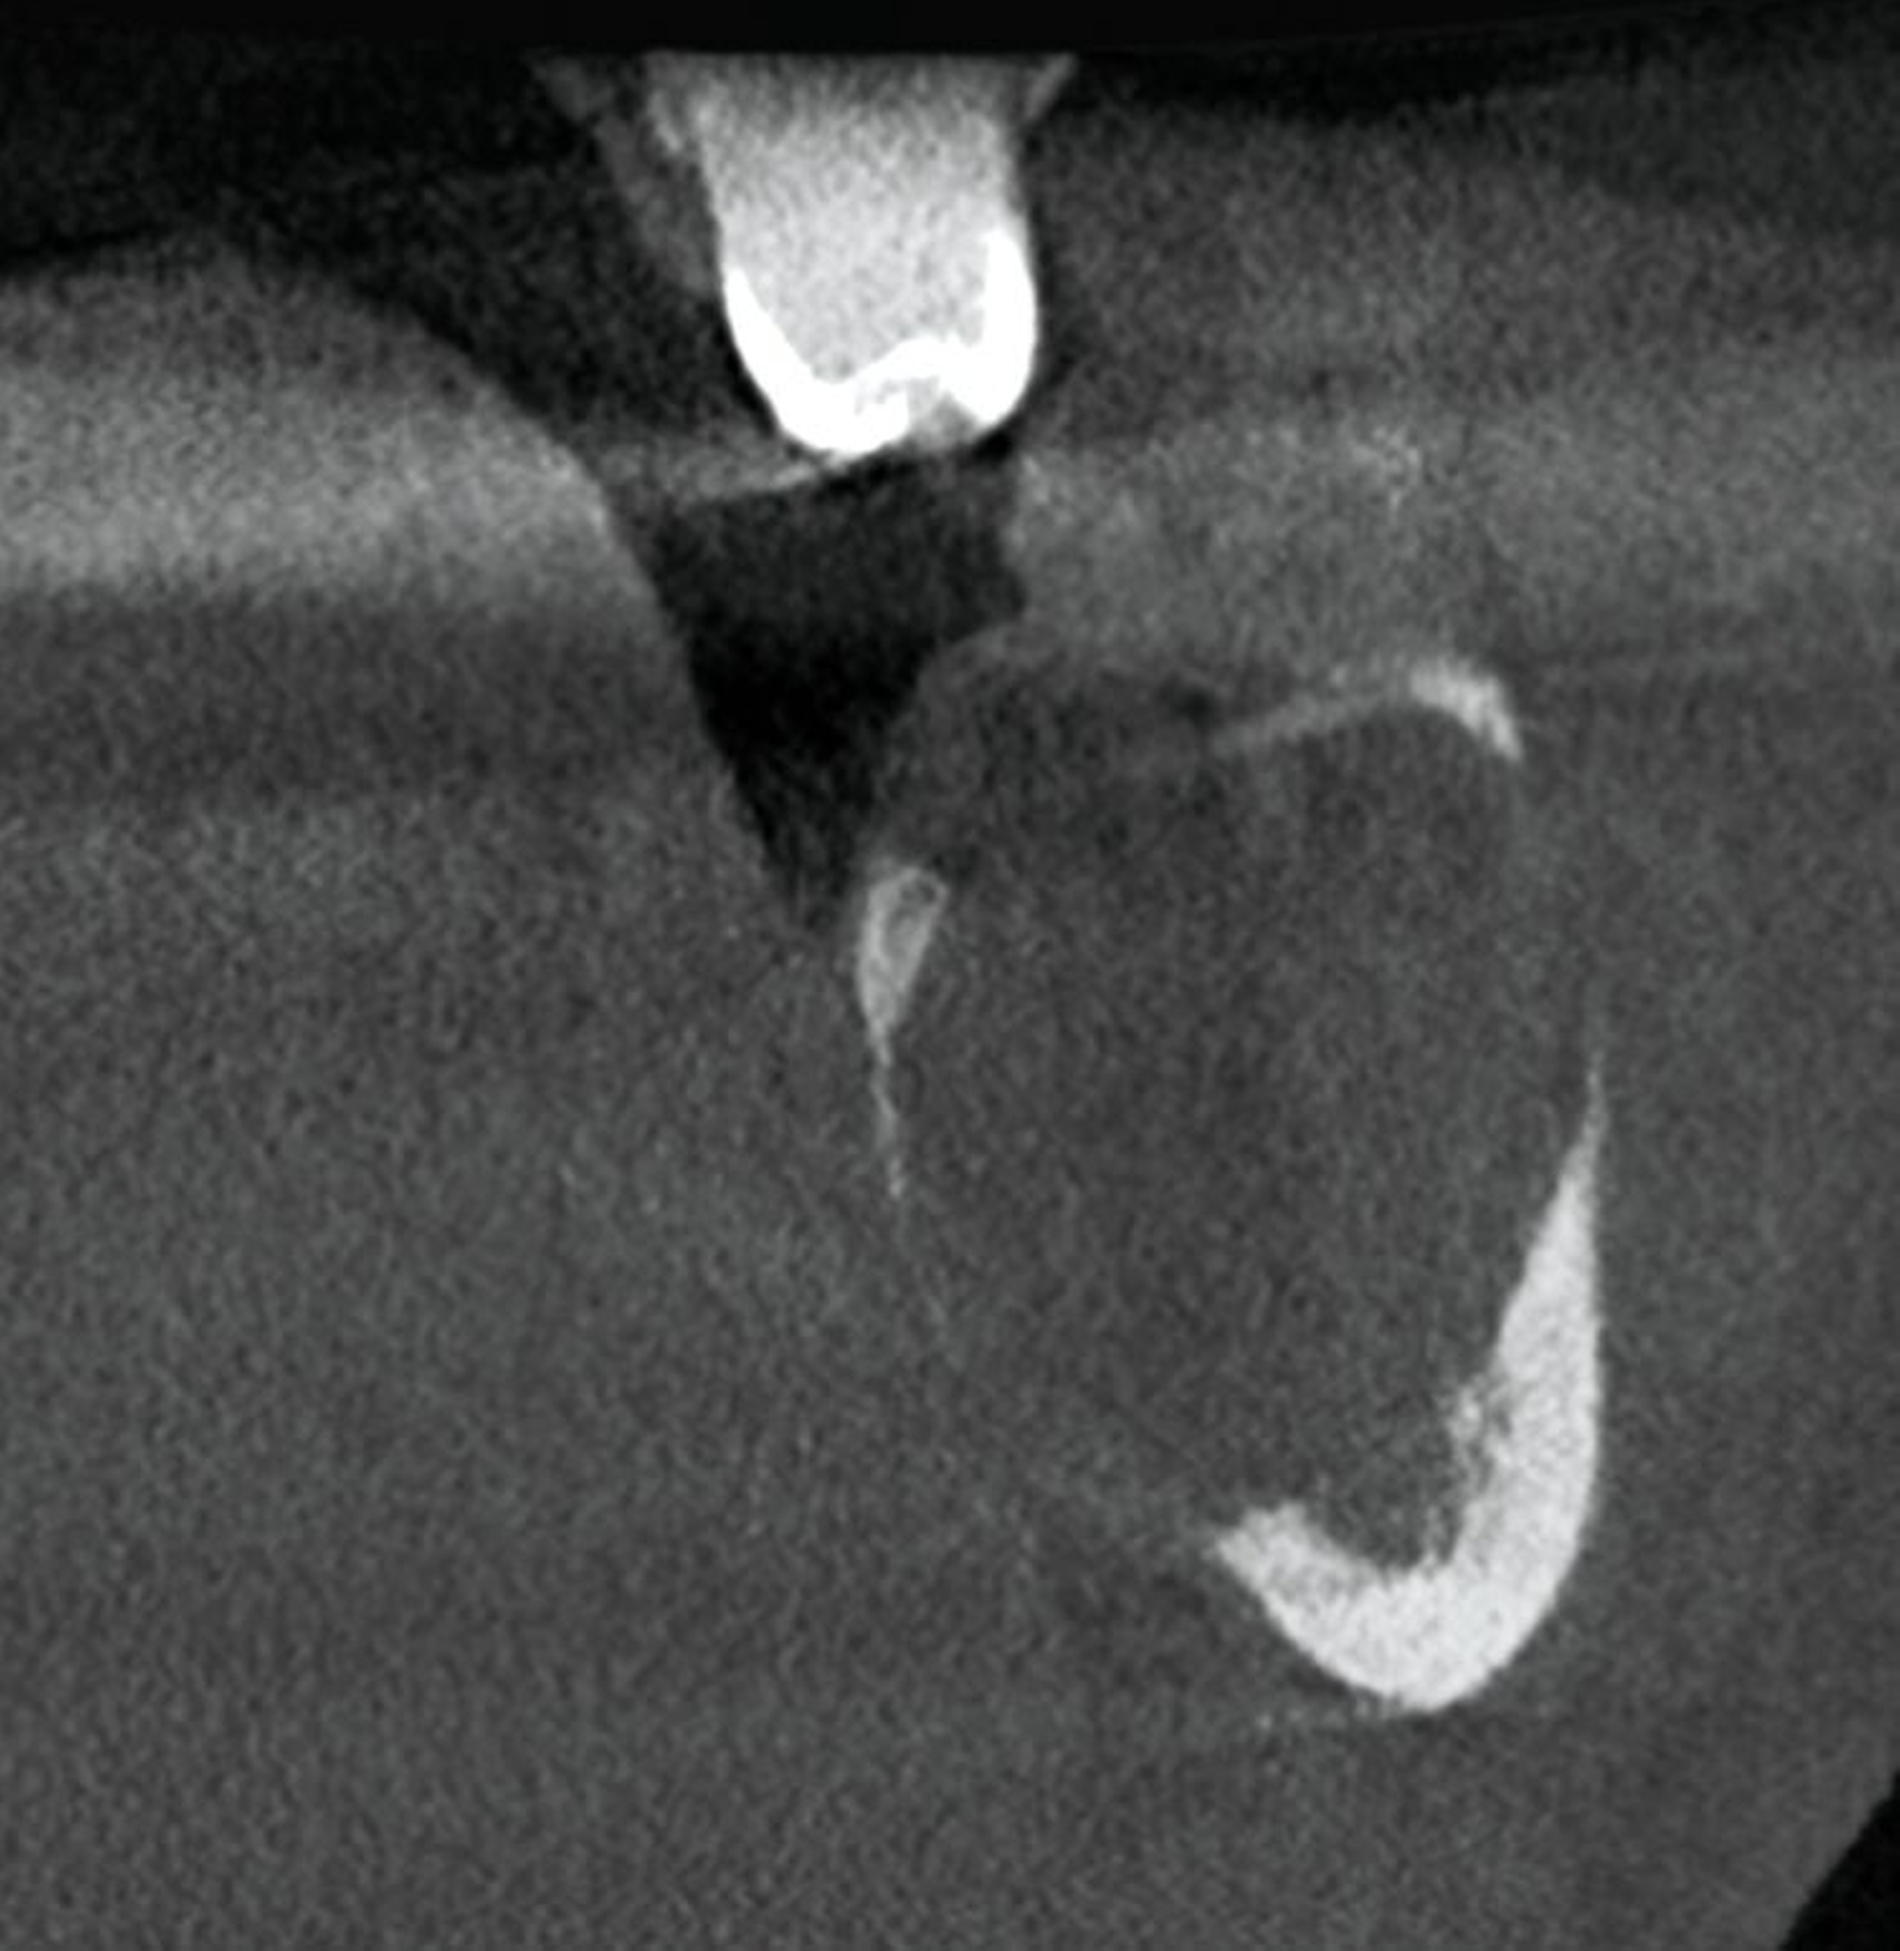

Die digitale Volumentomografie (DVT) ergab eine mehrkammerige, radioluzente Raumforderung, die sich bei erhaltener Kortikalis von der mesialen Wurzel des Zahnes 37 bis in den aufsteigenden Ast des Ramus mandibulae erstreckte (Abbildungen 1 und 2). Aufgrund der Morphologie bestand der Verdacht auf einen keratozystischen odontogenen Tumor, differenzialdiagnostisch auf andere odontogene Tumoren. Nach Aufklärung wurden die Extraktion des nicht erhaltungswürdigen Zahnes 37 sowie die Zystektomie geplant und zwei Wochen später in Intubationsnarkose durchgeführt.